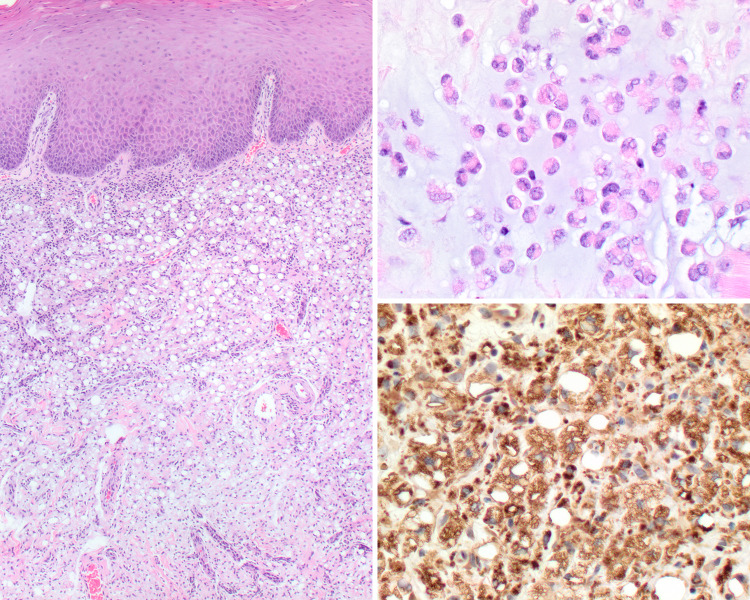

Fig. 2.

Salivary mucocele biopsy showing (left) submucosal mucus extravasation (H&E stain, medium magnification) (upper right) associated with abundant admixed histiocytes (H&E stain, high magnification). (Lower right) Muciphages are CD68 immunoreactive (Immunohistochemistry, high magnification)